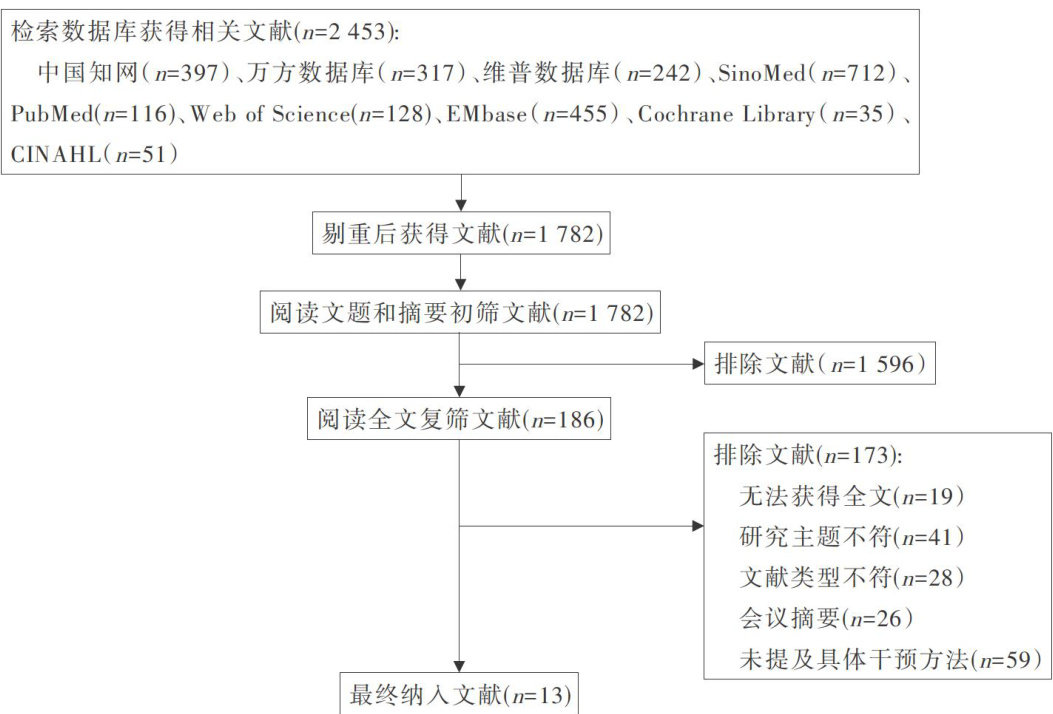

科研论著 | 早期饮水方案在心脏外科术后病人中应用效果的Meta分析

科研论著 | 早期饮水方案在心脏外科术后病人中应用效果的Meta分析